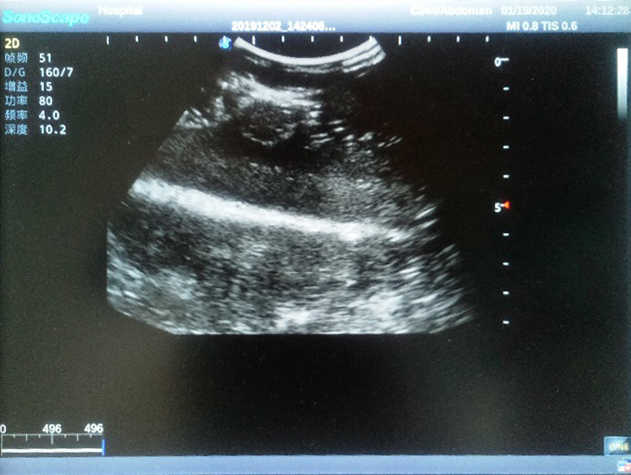

Model TYE1568

The Breast Ultrasound Examination Model allows users to develop and practice the skills necessary to gain proficiency in breast palpation, using ultrasound for normal and abnormal imaging and biopsy. It simulates adult female breasts with realistic size and appearance.

2)  Each model contains 8 space-occupying lesions of varying sizes, different in touch, elasticity and ultrasonogram

4) Biomimetic material allowing users to see clear and real normal tissues and space-occupying lesions that are hyperechoic, hypoechoic and isoechoic as they would see in the clinical environment